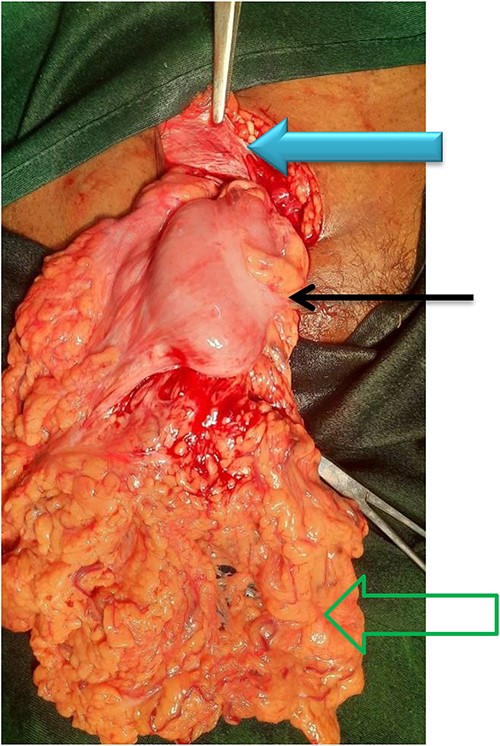

A 65-year-old multipara women presented with a groin mass of 2-year duration. She noticed it as a small painless bulge that used to disappear in a lying position, but during the last 2 months of her presentation, it failed to reduce. She had been feeling pressure symptoms and abdominal discomfort while walking and straining. She has been chewing chat two to three times per week for more than 20 years. She also had a history of constipation. She has no history of trauma, previous surgery, or known chronic illness. Physical examination showed a BP of 135/80, PR75, RR 18, and a BMI of 18.4. Abdominal examination revealed a 6 × 4 cm irreducible soft, nontender mass inferior to right inguinal ligament (Fig. 1). Bowel sound was audible from the mass. Ultrasound has confirmed the diagnosis of a femoral hernia. Other routine and baseline tests showed normal results. A diagnosis of incarcerated femoral hernia was made, and patient was prepared for elective herniorrhaphy.

Femoral hernia in a 65-year-old female patient (arrow showing a bulky mass inferior to inguinal ligament with a normal overlying skin).